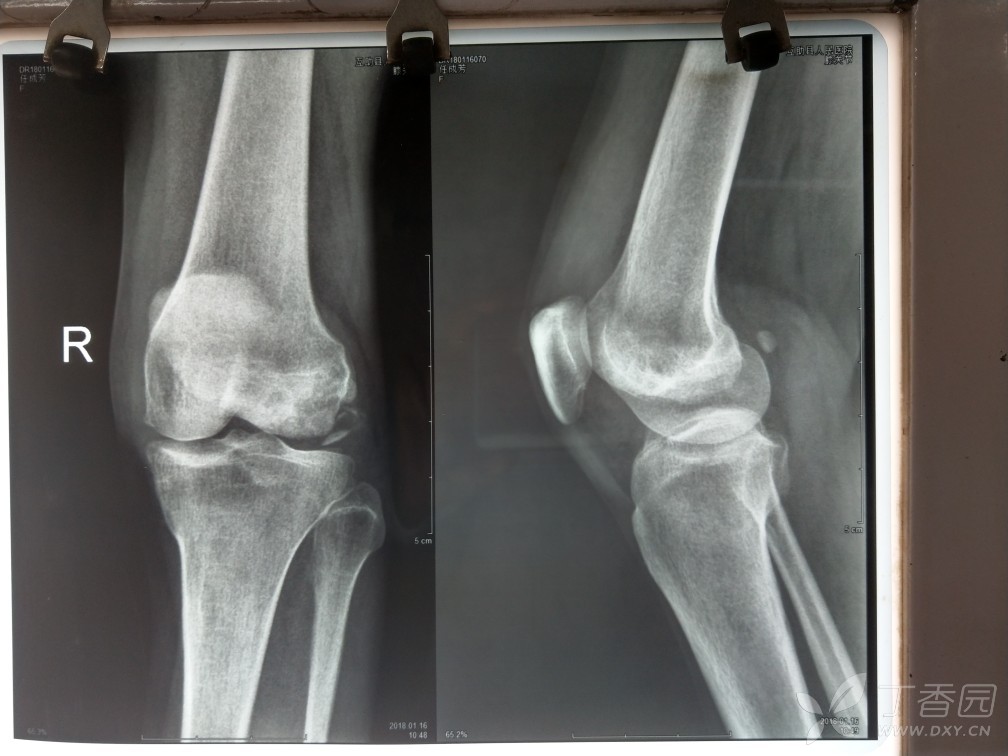

hoffa骨折? - 骨科专业讨论版 -丁香园论坛

图片尺寸1008x756